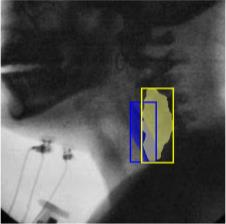

The videofluoroscopic swallowing study (VFSS) is a gold-standard imaging technique for assessing swallowing, but analysis and rating of VFSS recordings is time consuming and requires specialized training and expertise. Researchers have recently demonstrated that it is possible to automatically detect the pharyngeal phase of swallowing and to localize the bolus in VFSS recordings via computer vision, fostering the development of novel techniques for automatic VFSS analysis. However, training of algorithms to perform these tasks requires large amounts of annotated data that are seldom available. We demonstrate that the challenges of pharyngeal phase detection and bolus localization can be solved together using a single approach. We propose a deep-learning framework that jointly tackles pharyngeal phase detection and bolus localization in a weakly-supervised manner, requiring only the initial and final frames of the pharyngeal phase as ground truth annotations for the training. Our approach stems from the observation that bolus presence in the pharynx is the most prominent visual feature upon which to infer whether individual VFSS frames belong to the pharyngeal phase. We conducted extensive experiments with multiple convolutional neural networks (CNNs) on a dataset of 1245 bolus-level clips from 59 healthy subjects. We demonstrated that the pharyngeal phase can be detected with an F1-score higher than 0.9. Moreover, by processing the class activation maps of the CNNs, we were able to localize the bolus with promising results, obtaining correlations with ground truth trajectories higher than 0.9, without any manual annotations of bolus location used for training purposes. Once validated on a larger sample of participants with swallowing disorders, our framework will pave the way for the development of intelligent tools for VFSS analysis to support clinicians in swallowing assessment.